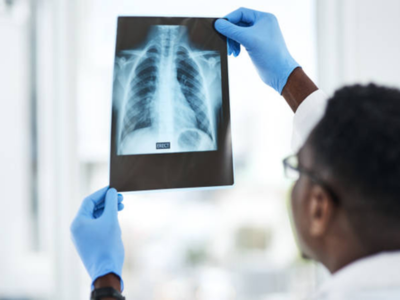

State-of-the-Art Cardiac Imaging & Diagnostics at Echelon Hospital

Early and precise diagnosis is the foundation of effective cardiology treatment in Navi Mumbai. Echelon Hospital is equipped with advanced diagnostic tools that help detect heart conditions at an early stage.

These technologies enable cardiologists to evaluate heart function, identify blockages, and assess overall cardiovascular health with accuracy.